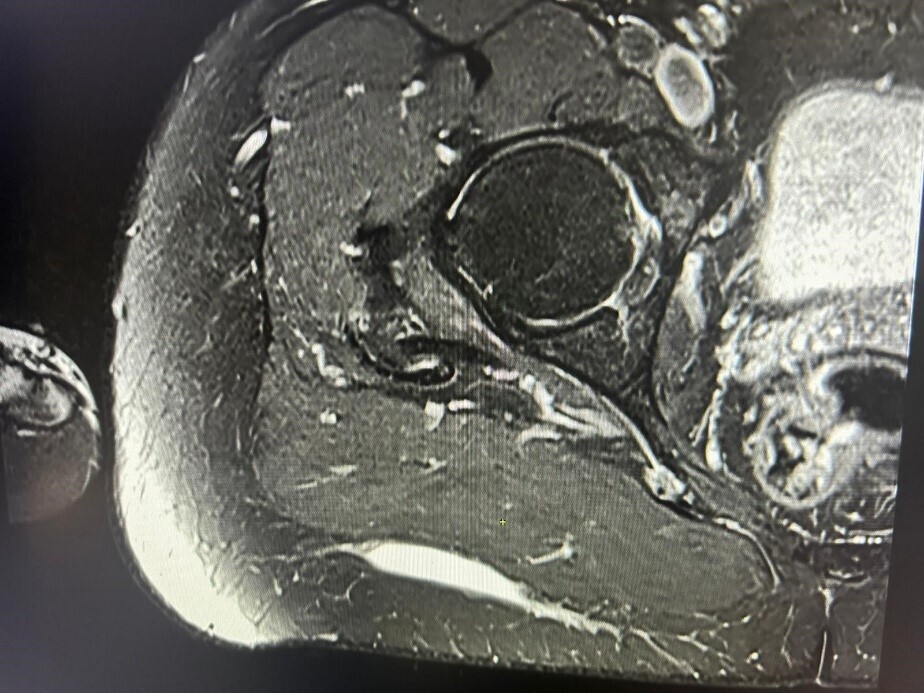

Une IRM est alors effectuée, concluant à une collection liquidienne évocatrice de saignement, sans capsule visualisée. Elle mesure 8,5 cm de grand axe et 0,6 cm de petit axe et est localisée en arrière du fascia musculaire superficiel du grand glutéal (fig. 3).

Devant l’aspect clinique de collection récidivante séro-hématique post-traumatique et l’aspect compatible en IRM, le diagnostic de syndrome de Morel-Lavallée est évoqué.

L’IRM est préconisée afin de catégoriser l’évolution de la collection : hyposignal T1 et hypersignal T2 à la phase aiguë, puis, au stade chronique, hypersignal T1 avec anneau périphérique cicatriciel en hyposignal T1, correspondant à la capsule fibreuse.3